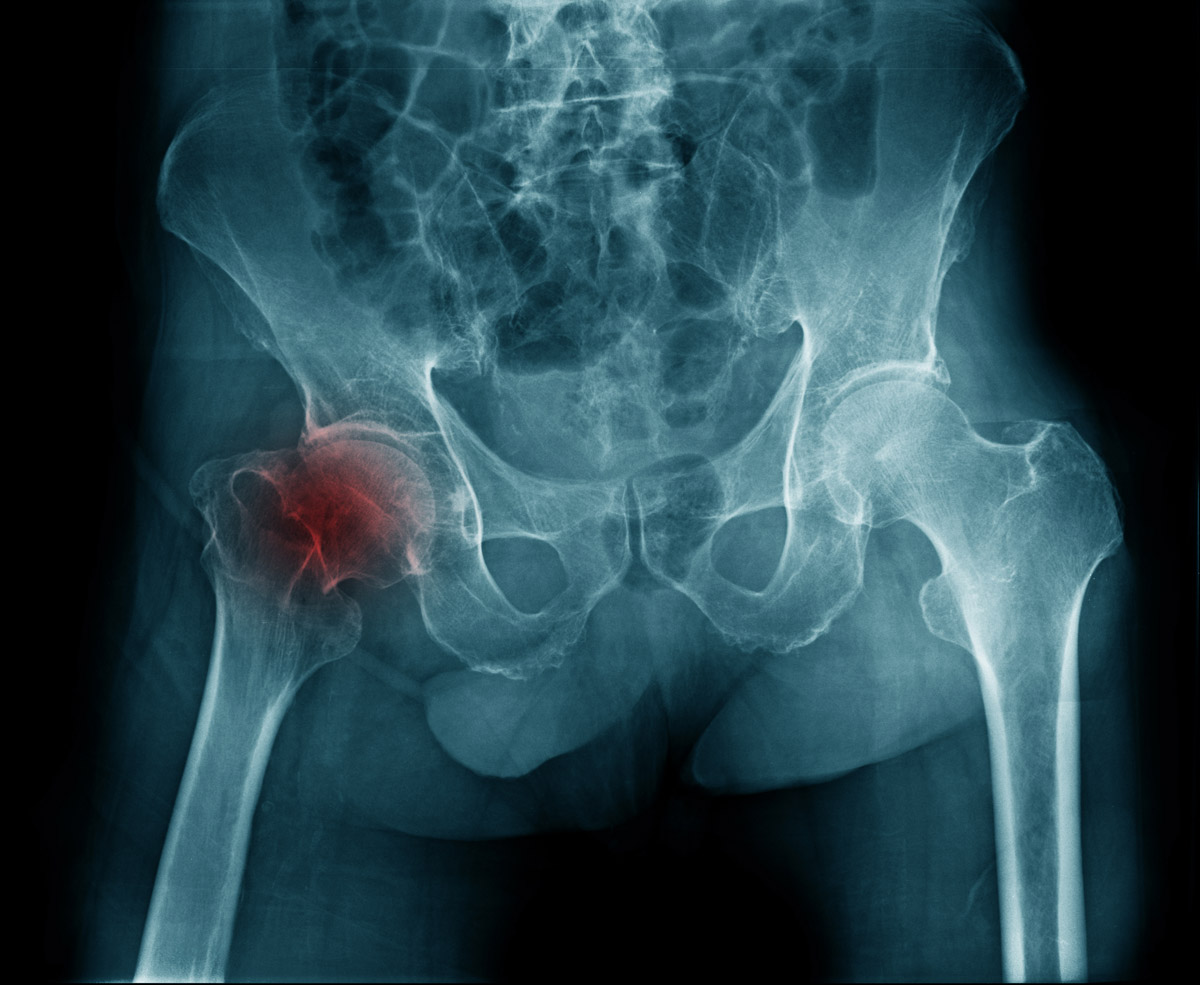

🦴 Что это такое?

Паралабральная киста — это полостное образование с жидкостью, которое формируется рядом с суставной губой тазобедренного сустава.

Чтобы понять механизм, вспомним анатомию.

Внутри тазобедренного сустава есть хрящевая «прокладка» — вертлужная губа. Она увеличивает глубину суставной впадины и стабилизирует головку бедренной кости.

Когда губа повреждается (надрыв, микротрещины), суставная жидкость начинает просачиваться наружу. Со временем формируется «карман» — киста.